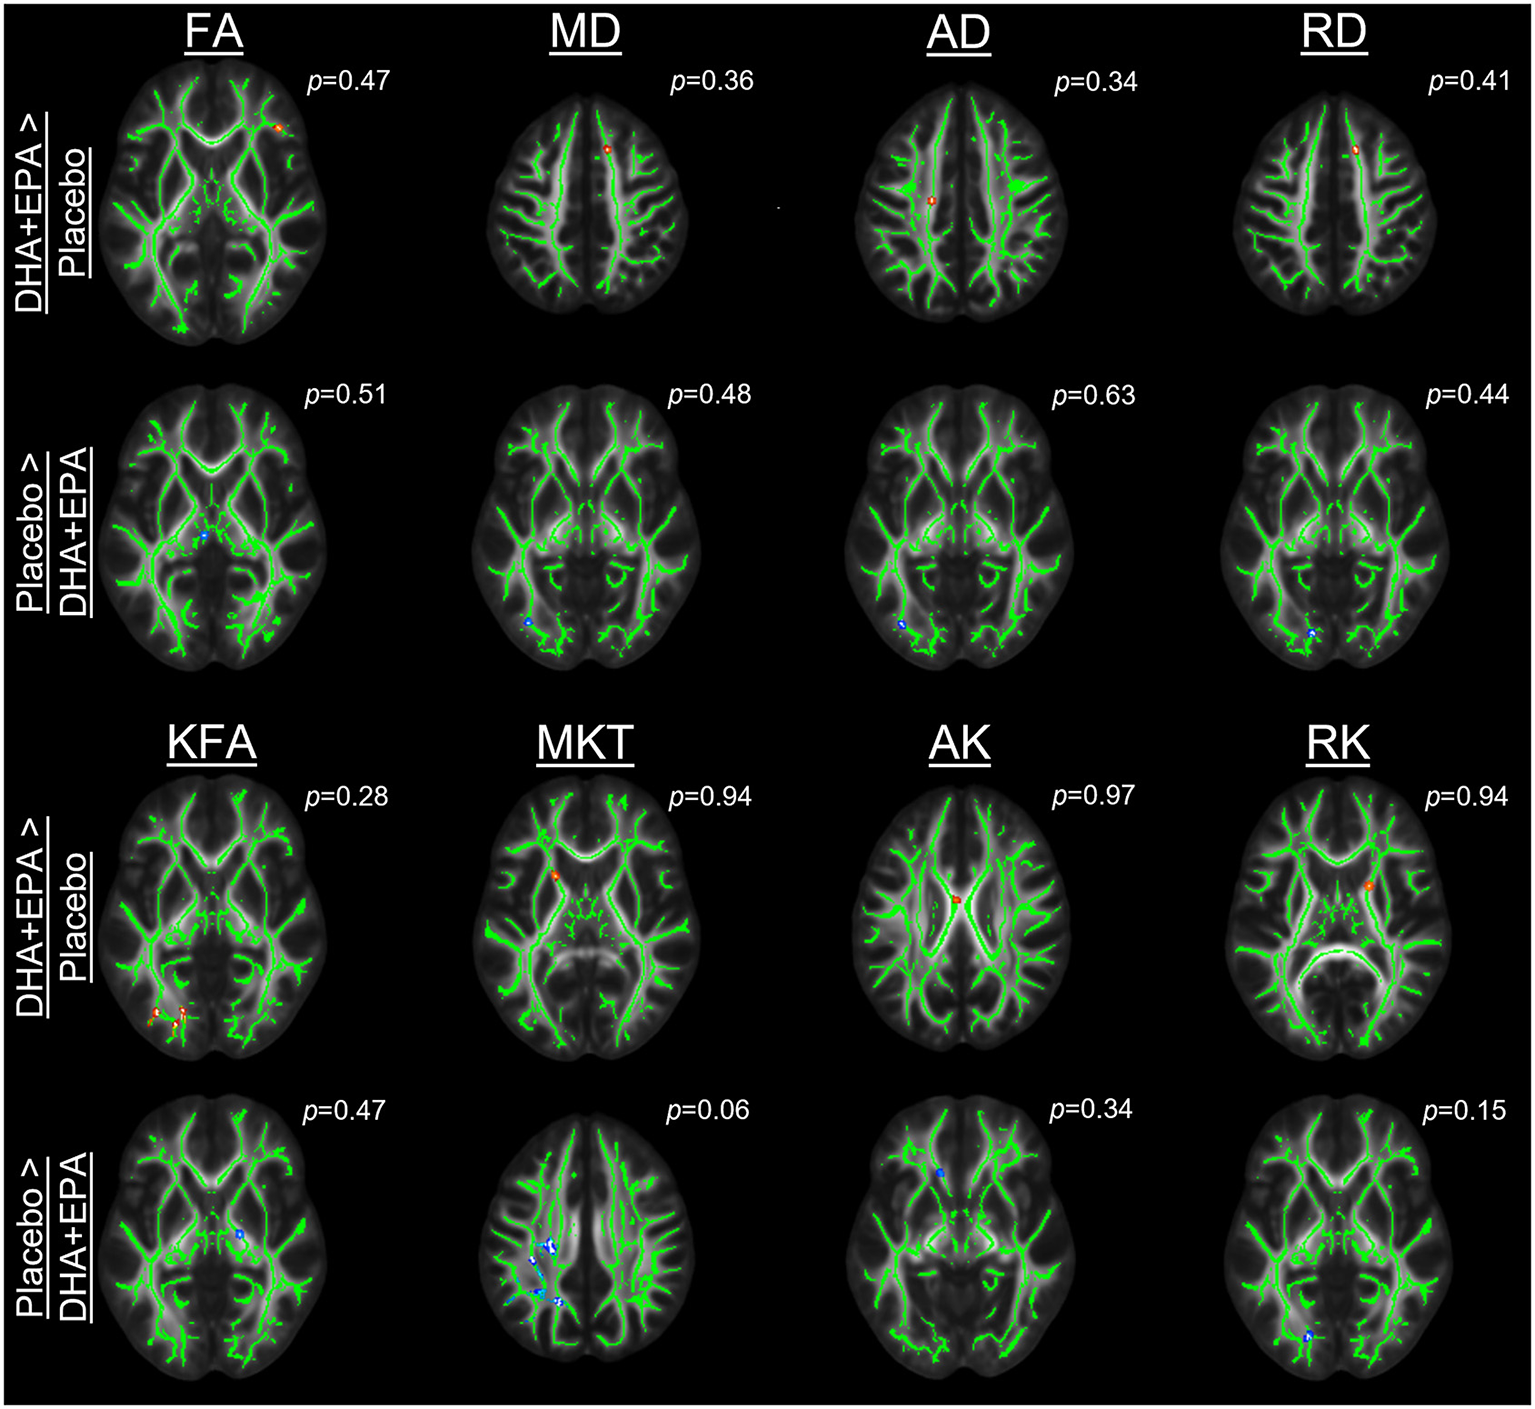

Axonal damage from football participation is not ameliorated by DHA + EPA supplementation

Outcomes of these analyses indicated no statistically significantly different changes in white matter metrics between placebo and DHA+EPA groups in any of the tensor-based voxel-wise analyses (Figure 2). However, for the mean of the kurtosis tensor (MKT), a cluster of voxels (n = 1,704; FWE corrected p ≤ 0.06) was identified in the superior and posterior corona radiata as well as superior longitudinal fasciculus where MKT increased in the placebo group (mean change = 0.049 ± 0.017) and decreased in the DHA+EPA group (mean change = −0.048 ± 0.059), though this cluster did not meet the a priori threshold for statistical significance.

Figure 2

Group-wise differences in diffusion tensor and kurtosis metrics following treatment. Changes in diffusion tensor and kurtosis metrics were evaluated between groups using tract-based spatial statistics. No statistically significant clusters were observed for diffusion tensor metrics (FA, MD, AD, RD). For diffusion kurtosis metrics, a cluster of voxels (n = 1,704) was identified where the placebo groups demonstrated a greater increase in the mean of the kurtosis tensor (MKT) than the DHA + EPA group. Other diffusion kurtosis metrics (KFA, AK, RK) revealed no differences. For each analysis, results are overlaid on the template brain with the skeletonized white matter voxels in green. Statistical images are presented for the smallest observed family-wise error corrected p-value for each contrast (DHA + EPA > Placebo: top contrast, red-yellow voxels; Placebo > DHA: bottom contrast, blue-light blue voxels).